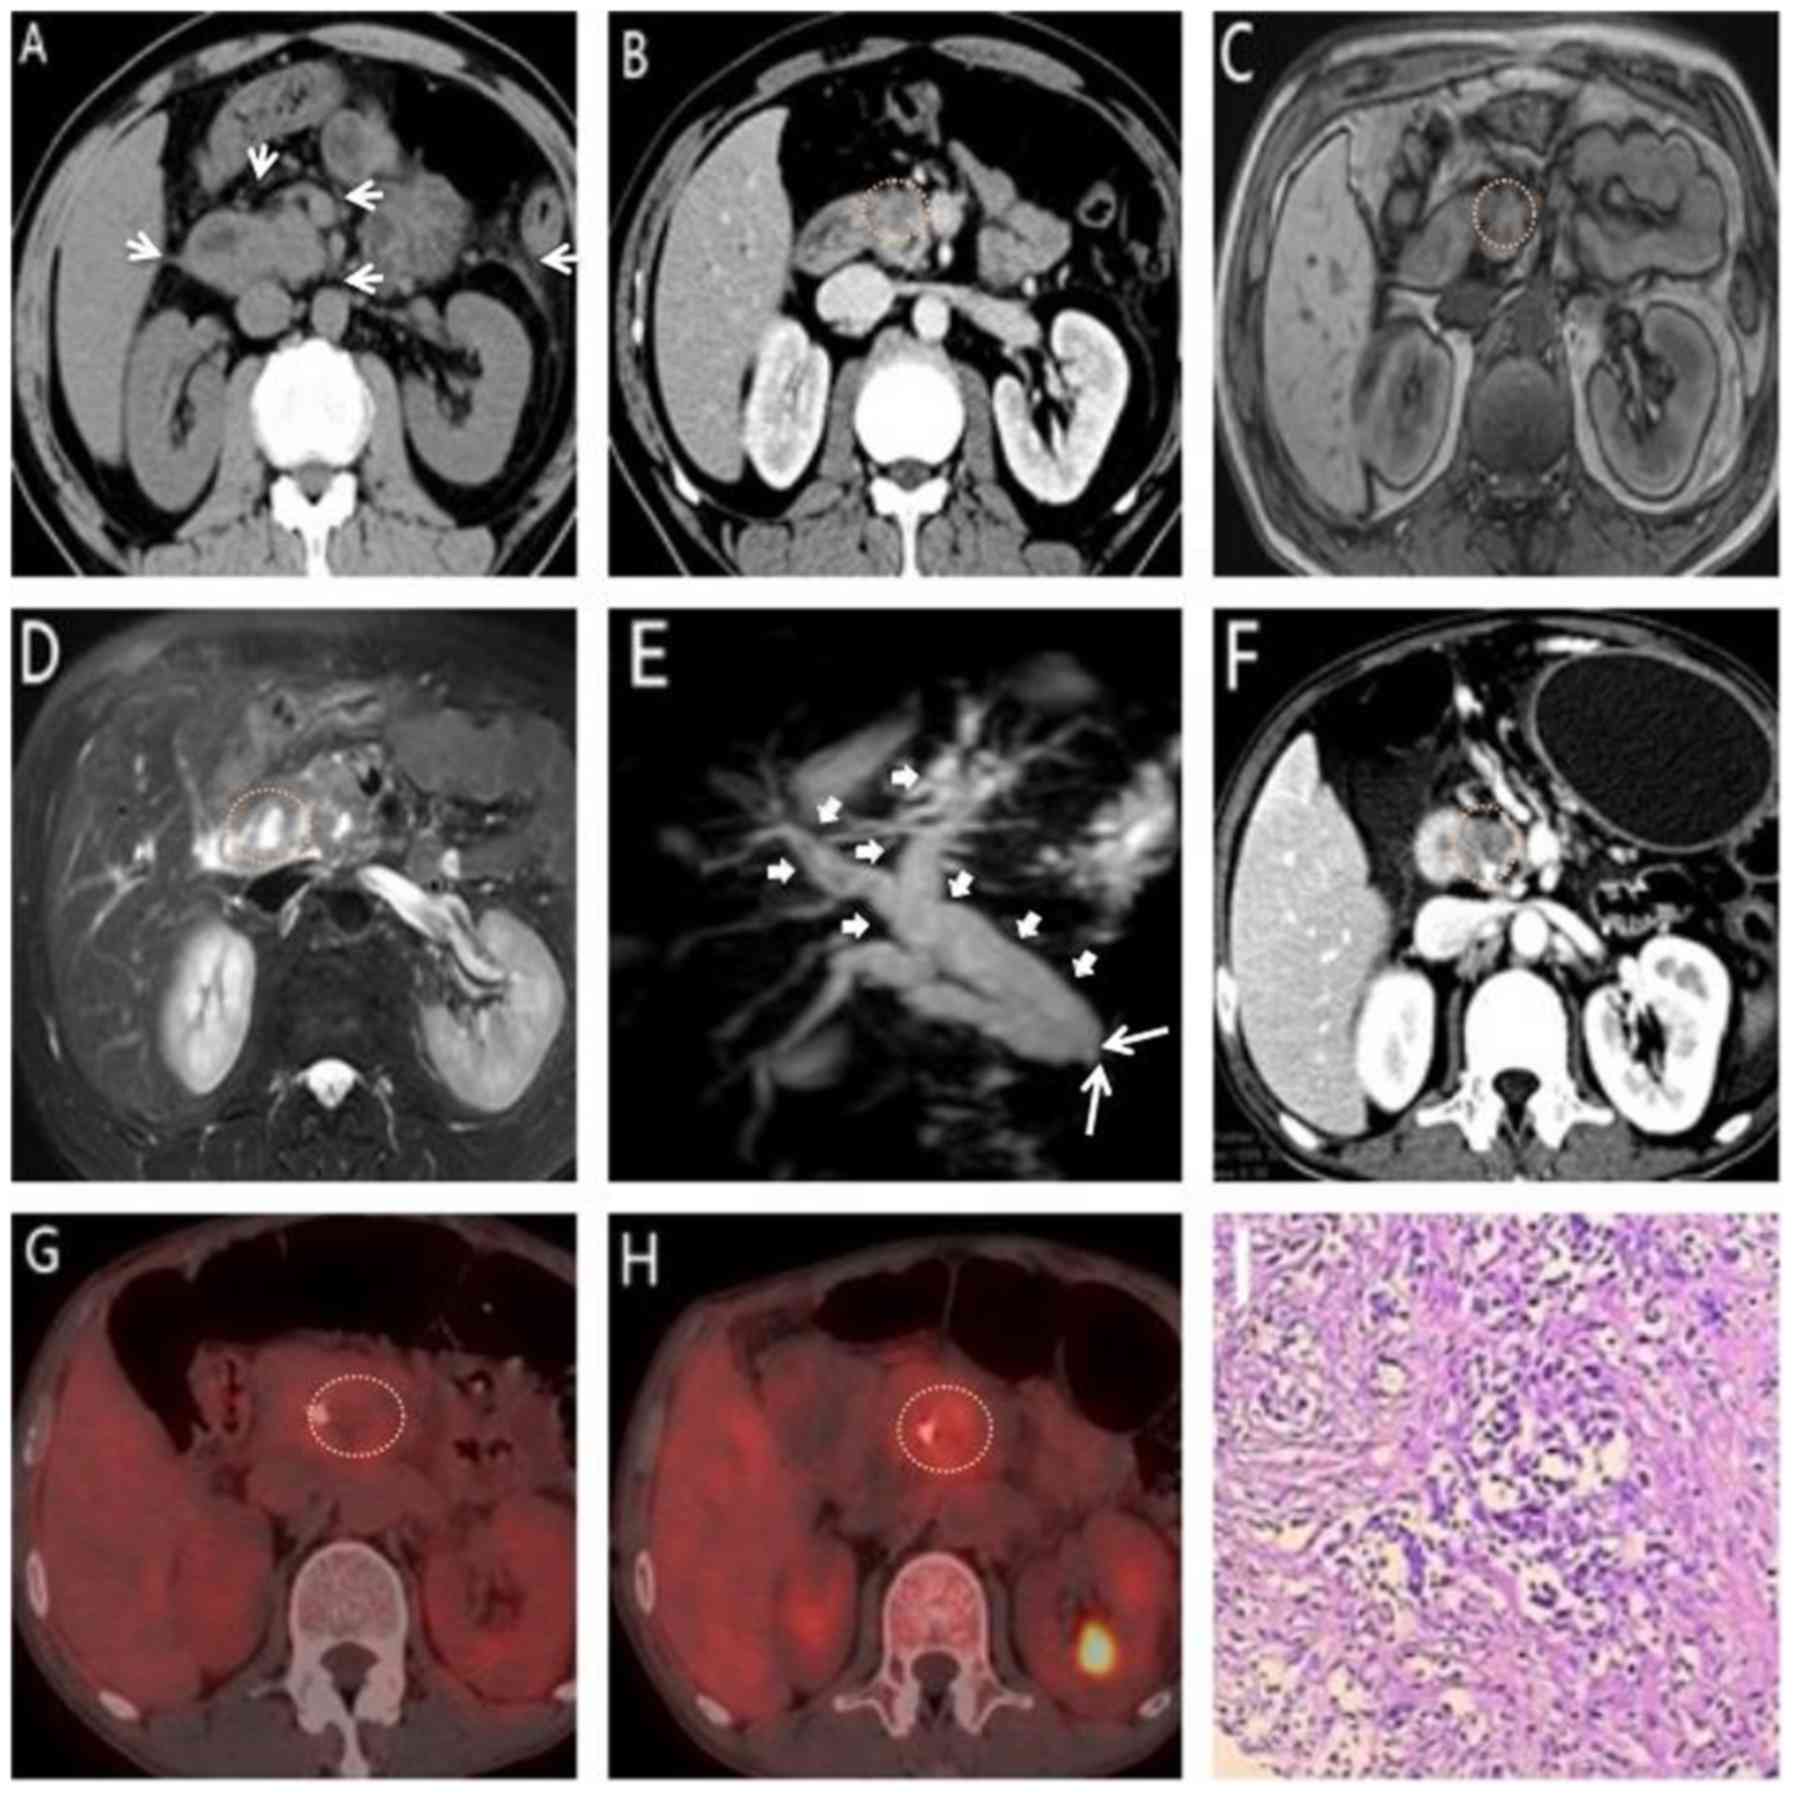

Comparison Of Mdct Mri And Mri With Diffusion Weighted Imaging In

Pdf Comparison Of Mdct Mri And Mri With Diffusion Weighted

Multi Modality Imaging Features Distinguish Pancreatic Carcinoma

Multi Modality Imaging Features Distinguish Pancreatic Carcinoma

Multi Modality Imaging Features Distinguish Pancreatic Carcinoma